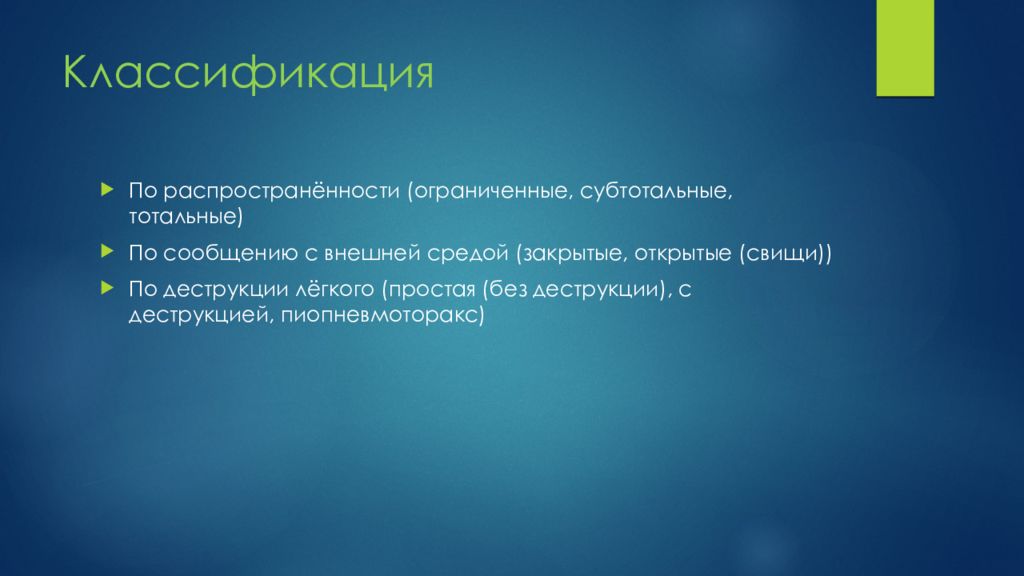

Дифференциальная диагностика заболеваний плевры